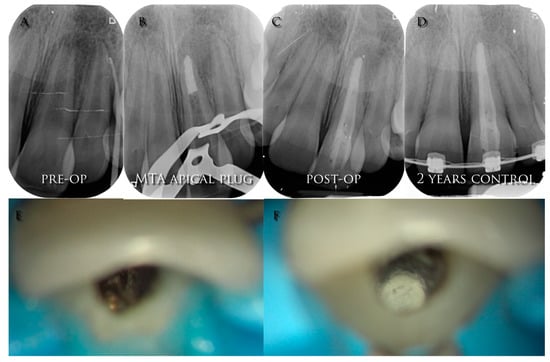

More recently, another type of apexification named as “apical MTA plug” was described using a new material, Mineral Trioxide Aggregate (MTA), a biocompatible powder with fine hydrophilic particles that hardens in the presence of humidity [], see Figure 2.

Figure 2.

(A) Pre-operative radiograph of a young necrotic upper left central incisor with open apex and a periapical lesion; (B) radiograph of the MTA apical plug; (C) post-operative radiograph; (D) 2-years control radiograph; (E) intra-operative image of the open apex; (F) intra-operative image of the MTA apical plug.